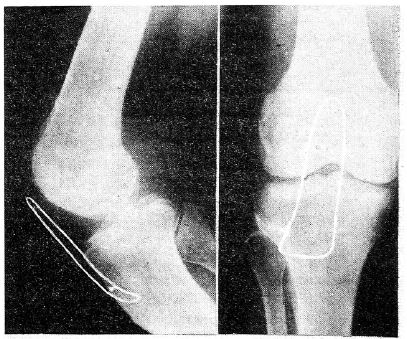

Такую «защищенную» пателлэктомию мы произвели у 3 больных. На рис. 4 показано расположение блокирующей проволочной петли.

Рис. 4. Рентгенограмма коленного сустава после пателлэктомии с блокированием.